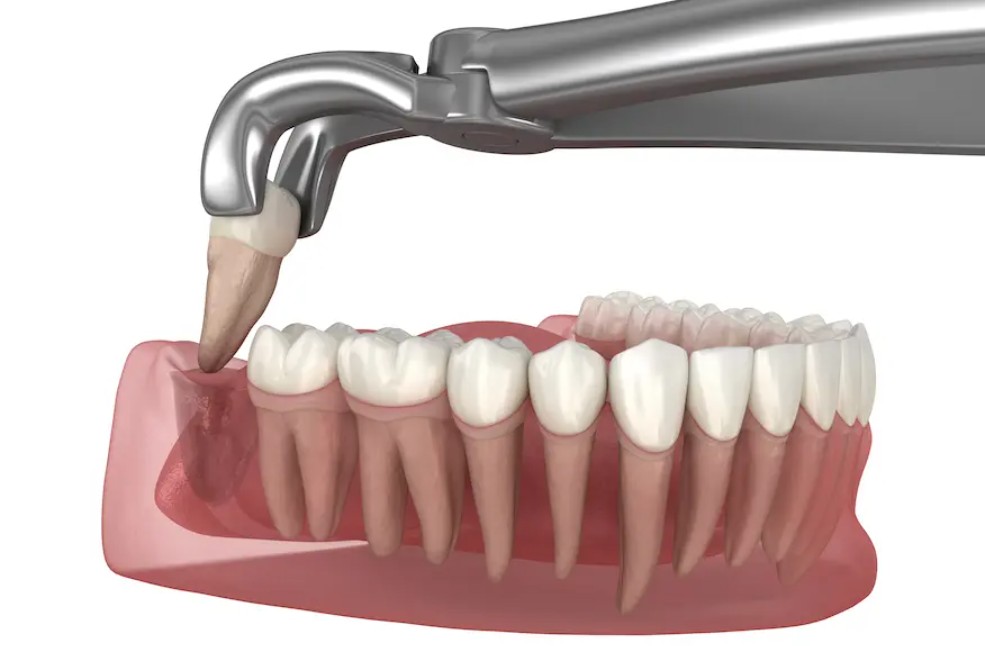

Trong nhiều trường hợp, nhổ răng khôn sớm là giải pháp hiệu quả nhất để chấm dứt đau nhức và phòng tránh biến chứng lâu dài. Quá trình nhổ răng hiện nay được thực hiện bằng công nghệ gây tê hiện đại, gần như không gây đau, thời gian lành thương nhanh hơn và an toàn tuyệt đối.